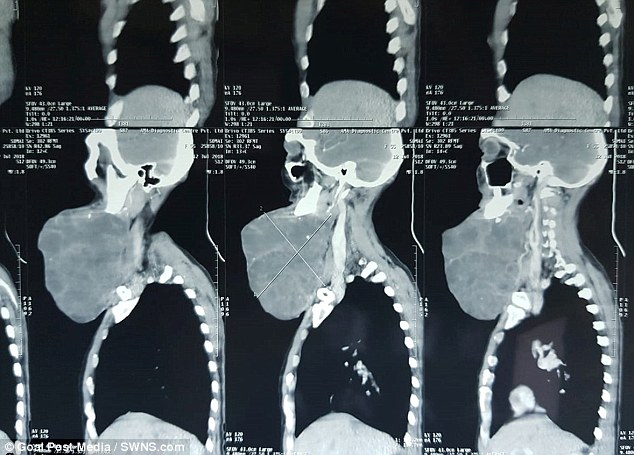

Khối u của bệnh nhân 55 tuổi này là nằm ở hàm dưới và liên quan đến tuyến nước bọt. Trong số những trường hợp có khối u hàm dưới như ông Somai, khoảng một nửa là lành tính, không chứa tế bào ung thư và hầu hết được điều trị bằng phẫu thuật.

Đây là một khối u ở xương hàm dưới và đang chèn vào động mạch cảnh - một loại động mạch chính ở vùng đầu và cổ, nó bao gồm những mạch máu quan trọng. Vì thế, bạn có thể cảm nhận nhịp tim khi đưa tay đặt lên cổ.

Khối u của ông Somai hình thành từ tuyến nước bọt, trong đó có 3 phần dọc theo quai hàm. Các khối u ở tuyến dưới thường có xu hướng nhỏ hơn và chỉ nằm ngay dưới hàm. Trong đó khoảng 10-20% những khối u tuyến nước bọt hình thành vị trí này và một nửa có thể chứa tế bào ung thư.

Nếu đó là những khối u nhỏ thì sẽ không quá khó khăn để phẫu thuật, nhưng khối u của ông Somai lại là khối u quá lớn nên phức tạp và tốn nhiều thời gian hơn. Sau phẫu thuật, khối u với trọng lượng lên tới 1,4 kg đã được loại bỏ. Đây là trường hợp khá hiếm gặp, tuy nhiên ca phẫu thuật thành công và hiện tại sức khỏe bệnh nhân đang dần ổn định.